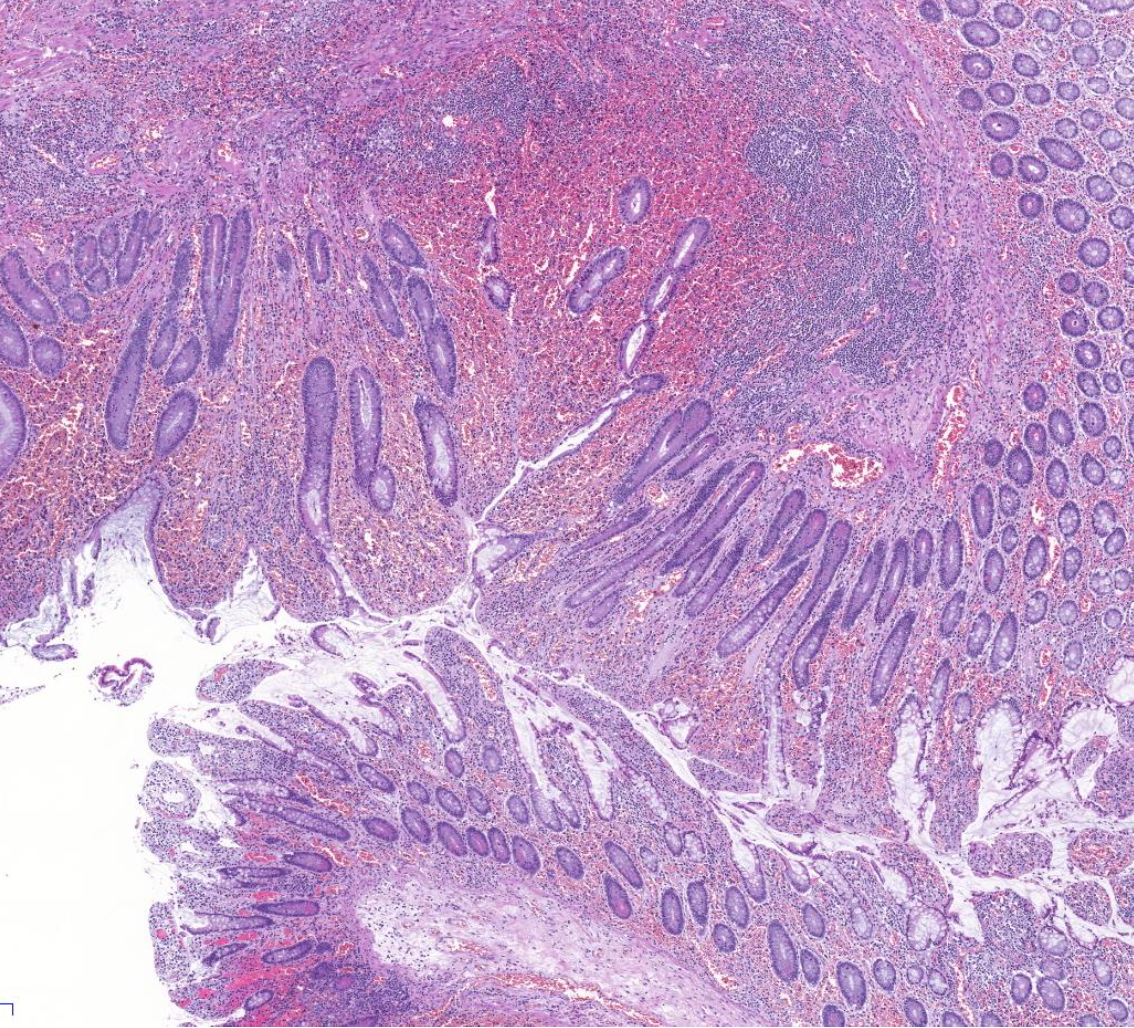

Diagnose?

Barettmetaplasie mit Dysplasie

-> Erkennt man an Becherzellen